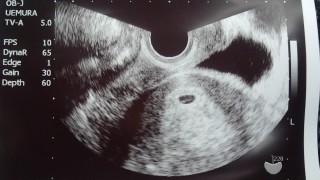

6週になり病院へ行ったら「排卵日遅れたかな?まだまだ小さいけど、これが袋だよ!」って。次は二週間後に予定日とか分かるみたい!!大きく育ってね!!(*^^*)

エコー写真

あなたのエコー写真と比べてみては...